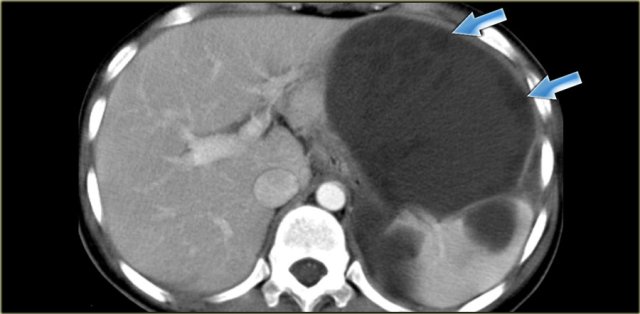

When these peritoneal inclusion cysts become very large, they may extend into the upper abdomen as is seen in the case on the left.

Notice that the left ovary is encircled by the cyst (arrow).

There are also some enhancing septa.